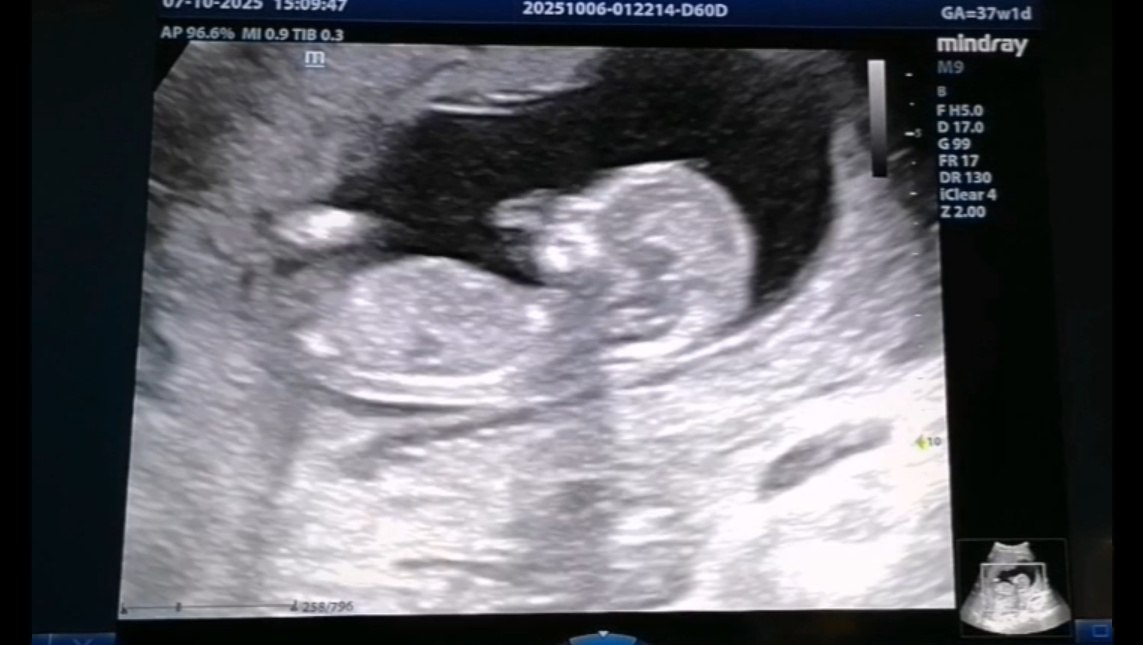

В Перинатальном центре Йошкар-Олы в отделении лучевой диагностики работает 7 врачей. 24 специалиста могут провести ультразвуковое исследование. Среди них врачи акушеры-гинекологи, неонатологи, реаниматологи-анестезиологи, рентгенолог.

Каждый рабочий день в центре проводится порядка 120 обследований.

фото: скрин